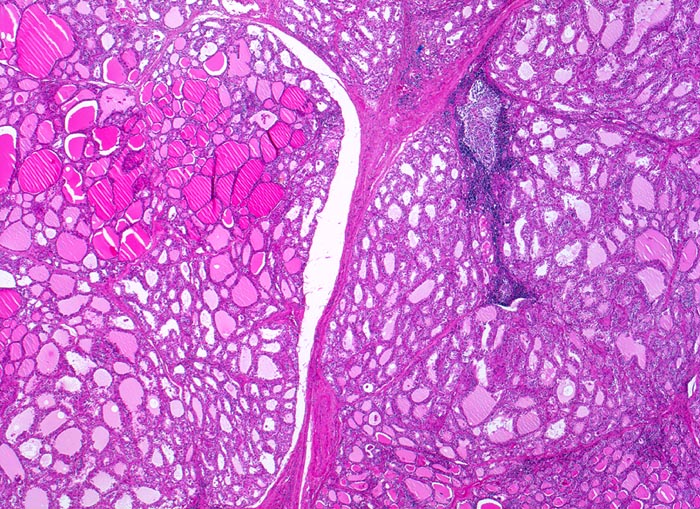

PathoPic – image database / PathoPic ID 4845 - Morbus Basedow

Morbus Basedow

Zwischen den einzelnen Schilddrüsenläppchen verlaufen schmale Bindegewebssepten. Vereinzelt sind Lymphfollikel mit Keimzentren vorhanden. Das Parenchym ist auffallend inhomogen. Neben hormonell wenig aktiven grossen Follikeln mit flachem Epithel und dunklem Kolloid finden sich zahlreiche Follikel mit Zeichen der gesteigerten hormonellen Aktivität: hochprismatisches Epithel, helles oder fehlendes Kolloid.

Das Vorhandensein von hormonell wenig aktiven Follikeln mit reichlich Kolloid beruht möglicherweise auf der vorausgegangenen thyreostatischen Therapie.